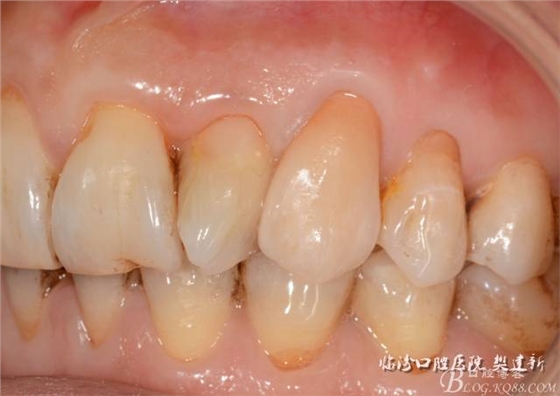

口內(nèi)檢查: 23殘根,位于齦上3MM,根管口探無(wú)反應(yīng),叩(+-),無(wú)松動(dòng),牙周無(wú)紅腫.X片示:23根管無(wú)阻射,根尖骨密度降低.11.12.13頸部楔形缺損,探敏感,牙髓活力正常.全口牙結(jié)石色素(+).

圖123口內(nèi)修復(fù)前情況:殘根位于齦上3MM,牙周無(wú)紅腫.